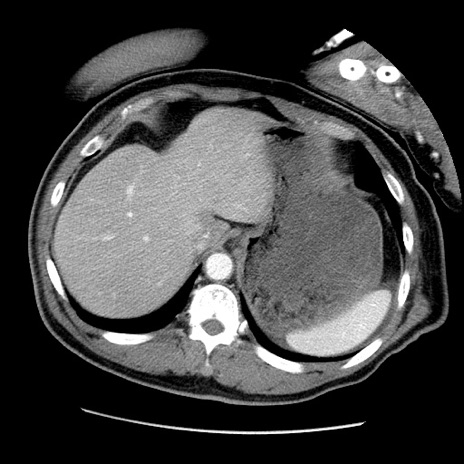

冠状断像

【症例】50歳代男性

【主訴】腹痛

【現病歴】AVMからの被殻出血のため回復期リハ病棟入院中。 本日午後3時頃急に下腹部痛が出現した。

【既往歴】AVM、被殻出血、虫垂炎、高血圧

【身体所見】意識晴明、左半身不全麻痺、会話の理解は良好、36.5°C、腹部:膨隆、全体に板状硬、下腹部正中に圧痛点あり、反跳痛-、筋性防御不明、右下腹部にope scar

【データ】WBC 9400、CRP 0.06